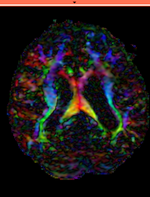

Registration Results (click to enlarge)

RegLib C03 baseline unregistered.gif

RegLib C03 baseline registered.gif

RegLib C03 DTI registered.gif

baseline & T2 before registration baseline to T2 after affine+nonrigid alignment DTI and T2 before & after registration